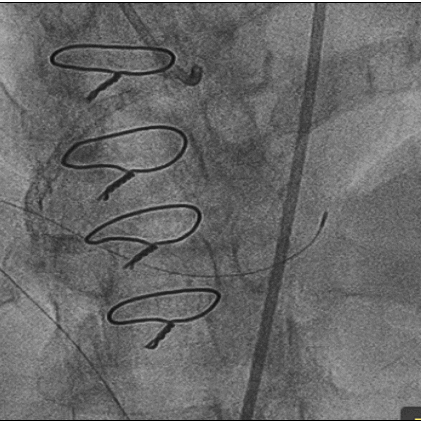

造影: